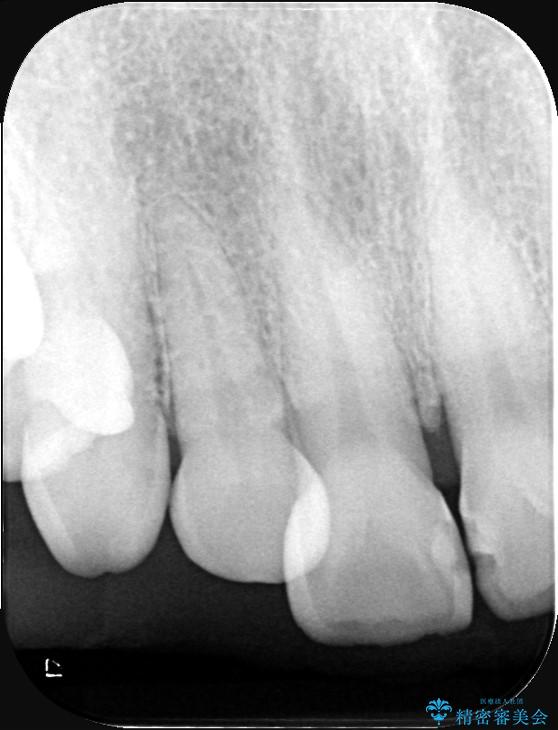

上下ともに軽度の叢生があり、下顎がやや前突傾向にあったため、本来であれば矯正治療が第一選択となります。矯正によって下の前歯を後方に移動させることで、咬み合わせの改善とともに前歯のデコボコも整えることができます。

そのため今回は、右上2番を抜歯し、右上1番および左上1番をオールセラミッククラウンで審美的に修復しました。

インプラント治療は、低侵襲で短期間に行える「抜歯即時インプラント治療」を選択しました。

この方法は、抜歯したその日にインプラントを埋入し、手術が1回で済むのが大きな特徴です。

治療期間も短く、抜歯からわずか3か月でオールセラミッククラウンを装着することができます。